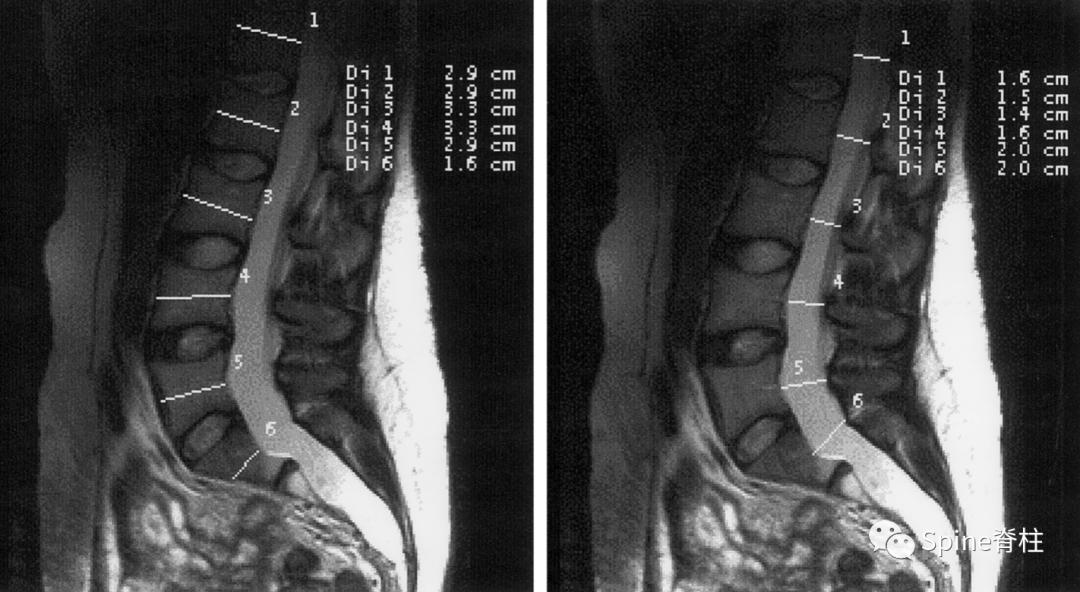

3. Oosterhof等 (PMID:11477262) 提出一个硬膜扩张的单一定量测量指标,即硬膜囊比 (dural sac ratio): 是指中段硬膜囊直径与椎体直径的比值。

正中矢状位所示中断椎体直径测量(左图)和硬膜囊直径的测量(右图)。L1-S1的硬膜囊比的临界值(cutoff values)分别为0.64、0.55、0.47、0.48、0.48和0.57。利用L3或S1的临界值,诊断硬膜扩张的敏感性为95%,特异性为98%。